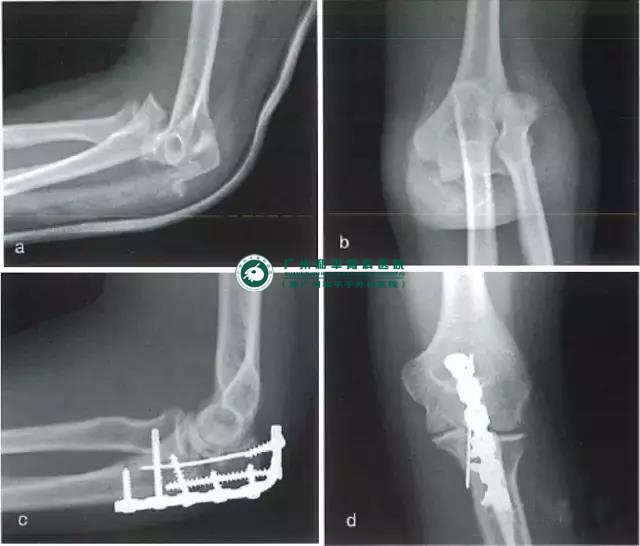

经尺骨鹰嘴的骨折脱位

肘关节屈曲90°时,来自前臂后方的直接高能量暴力可导致此类复杂肘关节损伤。必须将其与孟氏骨折区分开,前者的特点是桡骨与尺骨同时向前方脱位,而上尺桡关节保持完好。尺骨近端常常碎成多块,有一个大的冠状突骨块;合并桡骨头骨折的情况并不常见。其不稳定性主要是由于滑车切迹的破坏而不是肱尺关节脱位。侧副韧带可能被拉伤,但一般完整性存在。

手术采用后方入路,间接复位尺骨近端,方法与处理复杂鹰嘴骨折时相同。以1枚螺钉固定冠状突骨折块可增加稳定性。有时,冠状突完好但肘前关节囊撕脱,此时如果存在不稳定,需用铆钉修复。将塑形的重建钢板或3.5mmLCP钢板至于后侧,以支撑关节面,以及使用张力带钢丝环扎,都是可供选择的治疗方法。

a、伤后侧位片;b、伤后前后位片;c、术后侧位片;d、术后前后位片